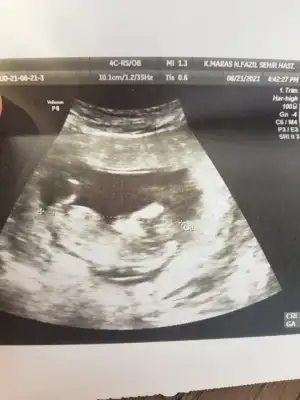

Erkek görünüyor

Yaaaa doktor kız demişti %85Erkek görünüyor![]()

Pardon cnm duzeltiyorum sanada erkek demis baska sayfada ❤Yaaaa doktor kız demişti %85bir oğlum var sağlıkla kız olsun çok isterim nub u kesin erkekmi

Kız görünüyorIkra meyra 12+4 canm

Önceki usg kaç haftalık bu kaç haftalik önceki daha net ise erkektir 11 12 13 haftalar olmalıTsk ederm canm önceki fotolarda erkek demistin ama sorun yok 1 ay sonra öğrenince oylayacagim anketini![]()

Bana göre hiçbiri net değilÖnceki usg kaç haftalık bu kaç haftalik önceki daha net ise erkektir 11 12 13 haftalar olmalı

Ikra meyra gecen sene kizimi tahminde dogru bilmistin canim 13+3haftalik gebeyim tekrardan var mi bi tahminin